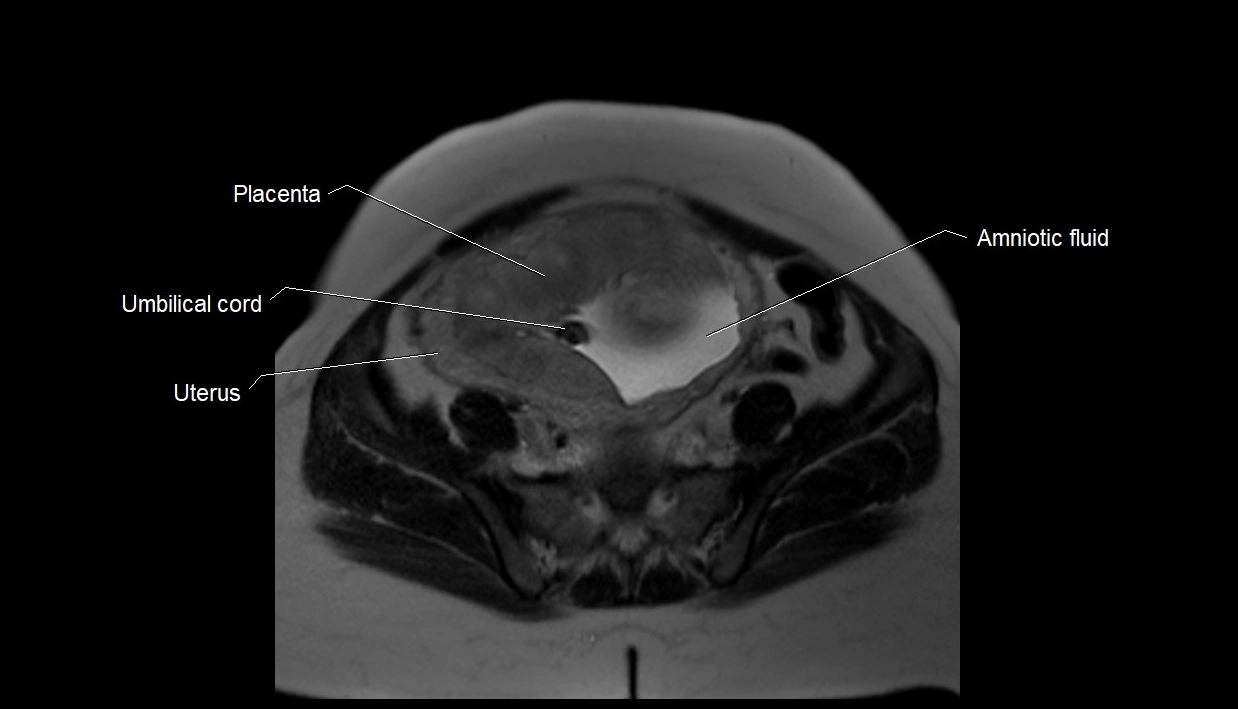

MRI Appearance

T2 HASTE (T2 GRE):

• Amniotic fluid shows very bright hyperintense signal

• Provides natural contrast against fetus and placenta

• Small particles (vernix) may appear as scattered hypointense foci within bright fluid

MRI image

image